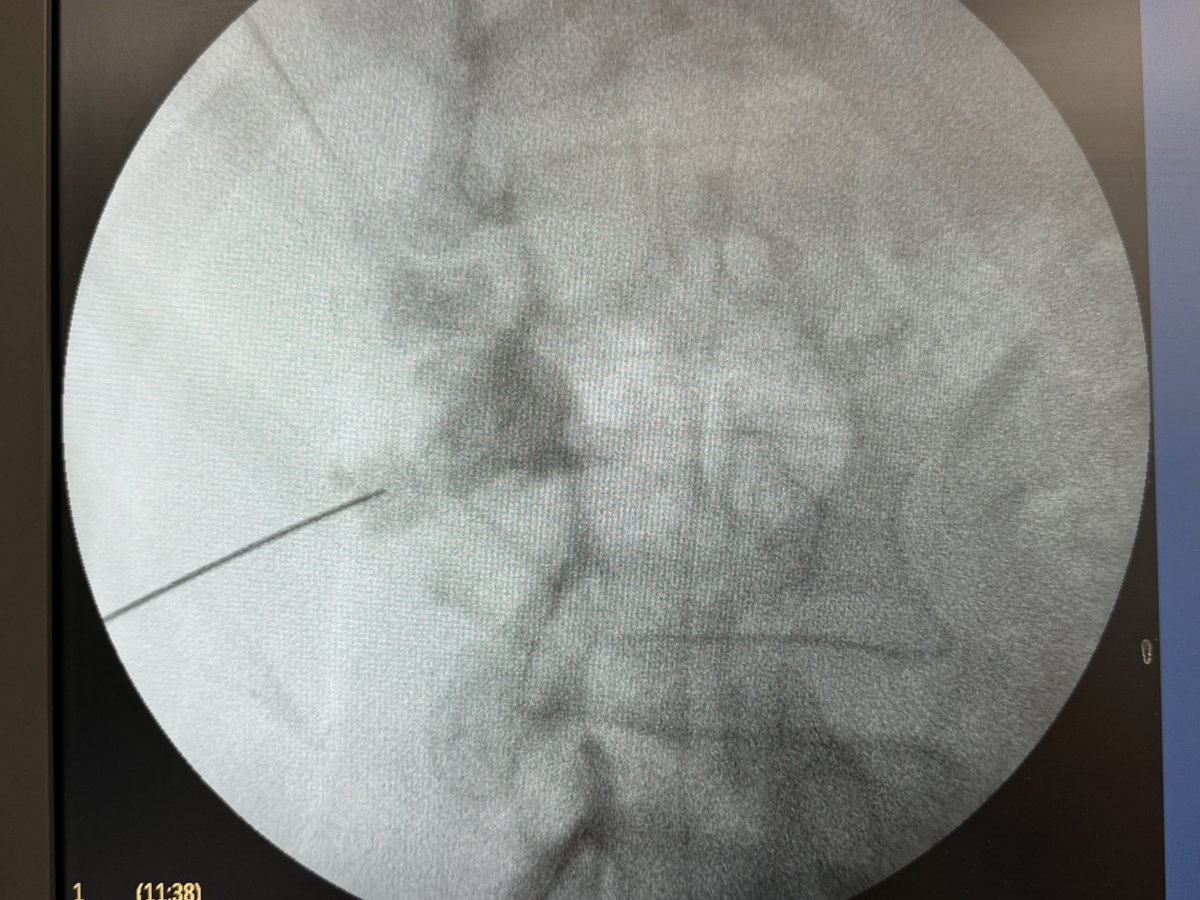

At last!! Long awaited Trilogy Max @EMSUrology arrives on the UK shores! Thanks to @BSCEMEA_Urology Lighter & more Ergonometric hand piece. Cordless foot pedal. Impressive and highly efficient stone fragmentation. 1300Hu staghorn calculi cleared in <7mins. #trilogymax #spinePCNL